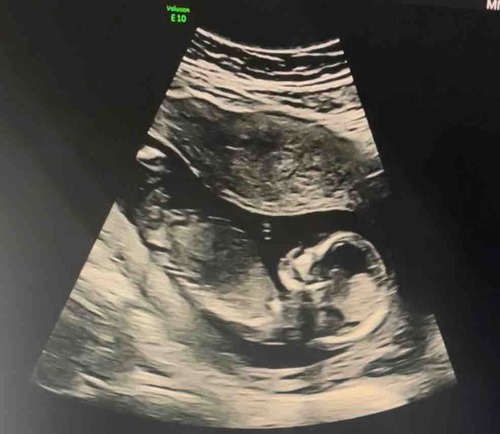

Maandag weten we eindelijk of het een meisje of jongen wordt 🥰 toch ben ik nieuwsgierig als jullie hier iets zien

Meisje

Denk ook een meisje